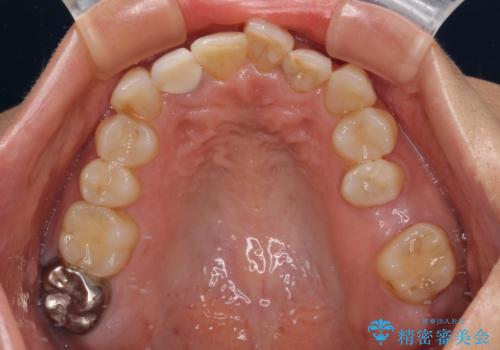

- 前歯のセラミッククラウンの縁が見えることが気になってから、デコボコも気になるようになってきたとのことで来院された患者様です。

デコボコの程度は中等度であったため、インビザライン・モデレートパッケージにて歯列を整えることとしました。

セラミッククラウンの装着されていた前歯と、大きな修復治療の跡がある反対側の歯は、矯正治療後に補綴治療を行うこととしました。

奥歯の欠損はインプラント、ブリッジ、入れ歯のどれにすれば良いかを決められず、仕事が非常にお忙しいこともあり、保留としたまま治療を終えることとなりました。